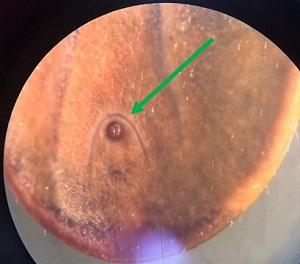

A 55-year old man from Massachusetts removed a tick attached to his forearm after returning from a weekend camping trip. He then took it to his county health clinic from where it was subsequently sent to the State Public Health laboratory for identification. Figure A shows a dorsal view of the tick, while Figure B shows the ventral side. Figure C and D shows a close-up of the mouthparts while Figure E is a close-up of the lower ventral side. What is your identification? Based on what criteria? What is the public health importance, if any, of this genus in North America?

Figure E